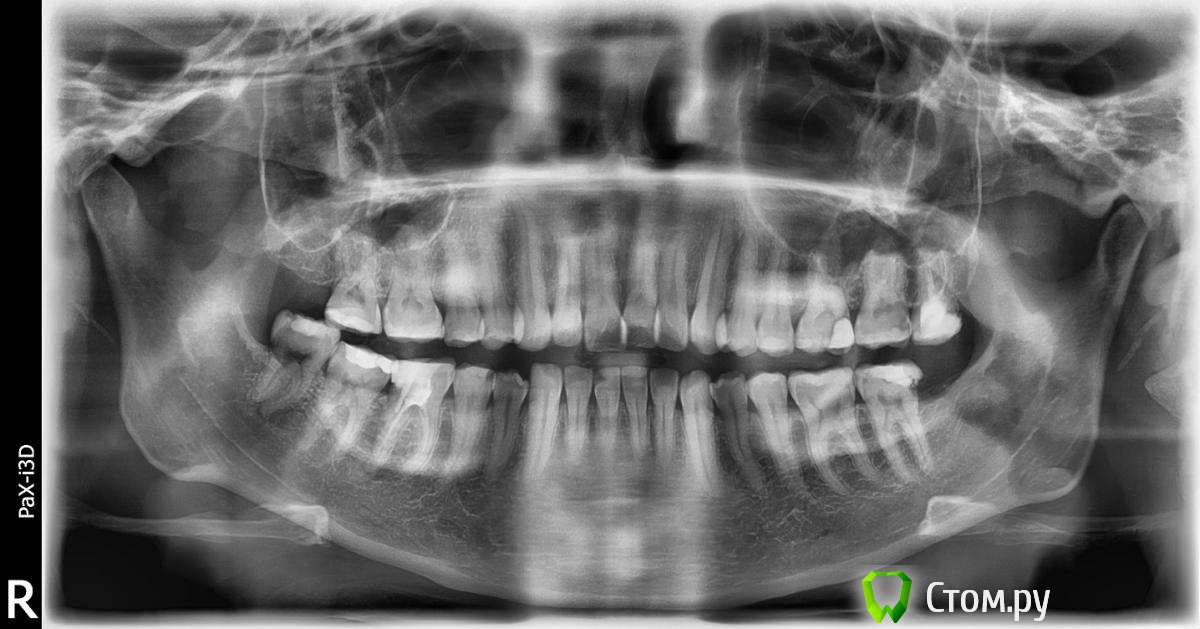

Force Опубликовано 17 августа, 2014 Поделиться Опубликовано 17 августа, 2014 Удаление и дистализация - вряд ли. Проблема больше с нижней челюстью, возможно вовлечен и сустав, судя по рентгенам. Непростая ситуация, возможно, что ортогнатическая коррекция окажется приоритетным вариантом. Но нужна более тщательная диагностика. 1 Ссылка на комментарий